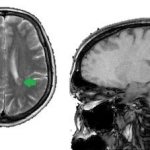

- Беспокойный сон может указывать на наличие рахита, энцефалопатии, опухоли головного мозга.